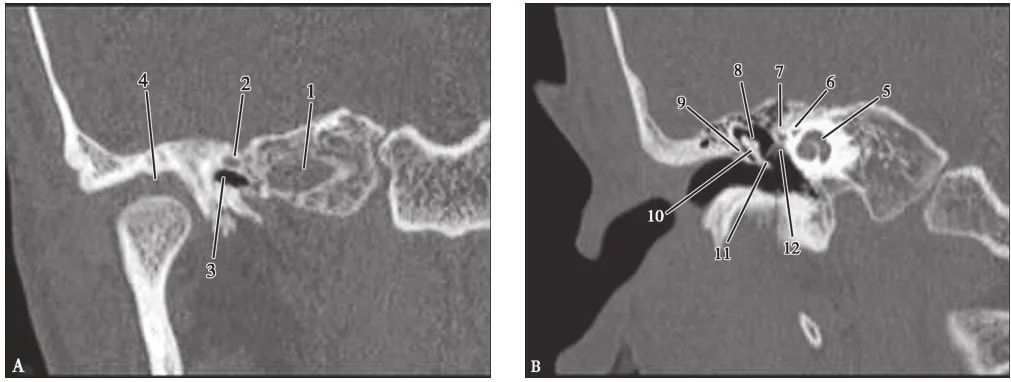

耳部及其周围的重要解剖结构 (CT横断面)

A.上骨半规管层面;B.外骨半规管层面;C.前庭窗层面;D.耳蜗层面;E.颈动脉管层面1.上骨半规管;2.弓形下窝;3.总骨脚;4.后骨半规管;5.外骨半规管;6.内耳道;7.耳蜗;8.面神经管迷路段;9.膝状神经节;10.前庭;11.上鼓室;12.乳突窦入口;13.乳突窦;14.鼓膜张肌;15.锤骨头;16.砧骨体;17.前庭窗;18.前庭导水管;19.圆窗;20.鼓岬;21.锤骨颈;22.砧骨长脚;23.面神经隐窝;24.锥隆起;25.鼓室窦;26.颈动脉管;27.咽鼓管;28.耳蜗导水管;29.颈静脉球